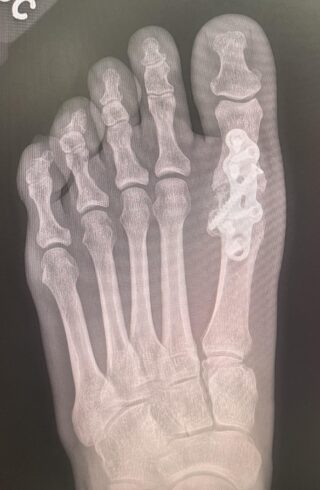

THE RELJA MTP PLATING SYSTEM

STABLE AND SECURE POSITIONING

MTP PLATES

AND SCREWS

Anatomically contoured titanium plates (XS, Medium)

Low profile 1.3mm thickness featuring a compression slot

Compatible with 3.5 mm locking and non-locking screws

Cup and cone reamers available

Optional 3.5 headed and 4.0 headless titanium cannulated screws